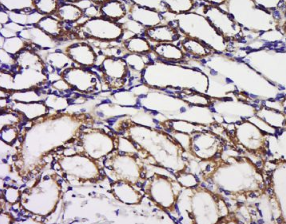

组织/细胞:小鼠肾组织;4%多聚甲醛固定石蜡包埋;

抗原提取:柠檬酸缓冲液(0.01M,pH 6),15min煮沸,用3%过氧化氢阻断内源性过氧化物酶30min;37℃下阻断缓冲液(正常山羊血清)20 min;

孵育:抗bpnt1多克隆抗体,未结合1:200,4°C下过夜,然后与二级抗体结合,DAB染色。